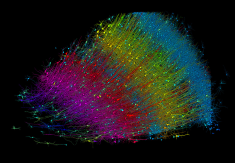

使用MultiSEM對1 mm

3人腦皮層組織進行高分辨成像,并對其中的各種細胞結(jié)構(gòu)進行三維重構(gòu)分析。左圖展示了2 x 3 mm

2組織平面中錐體神經(jīng)元的三維重構(gòu)效果。右圖顯示了局部體積神經(jīng)元三維重構(gòu)。圖像由哈佛大學(xué)Lichtman 實驗室提供,渲染圖由D. Berger 制作。